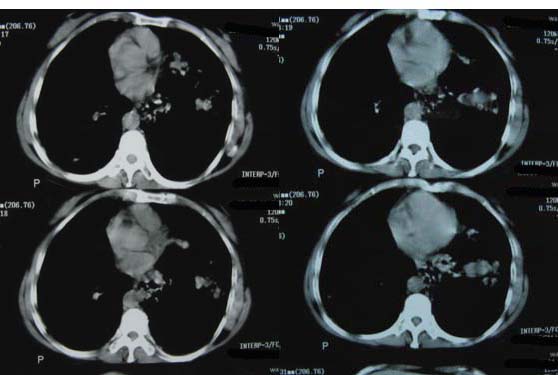

肝癌、肺转移。

1双肺支气管扩张  2双肺多发块状影,考虑:转移瘤;3肝门区圆形软组织影,先考虑:转移淋巴结可能性大.

肝癌、肺转移 支持

1肺转移瘤 2肝门区圆形软组织影,考虑淋巴结转移